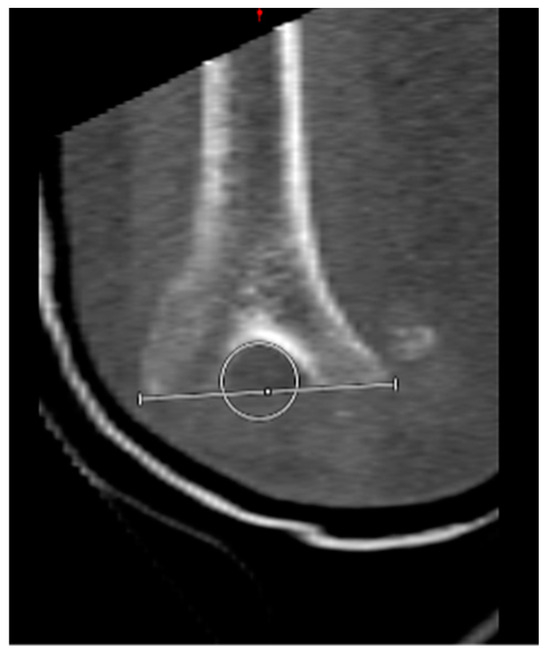

2.4. CT Image Analysis

3.5. Complications